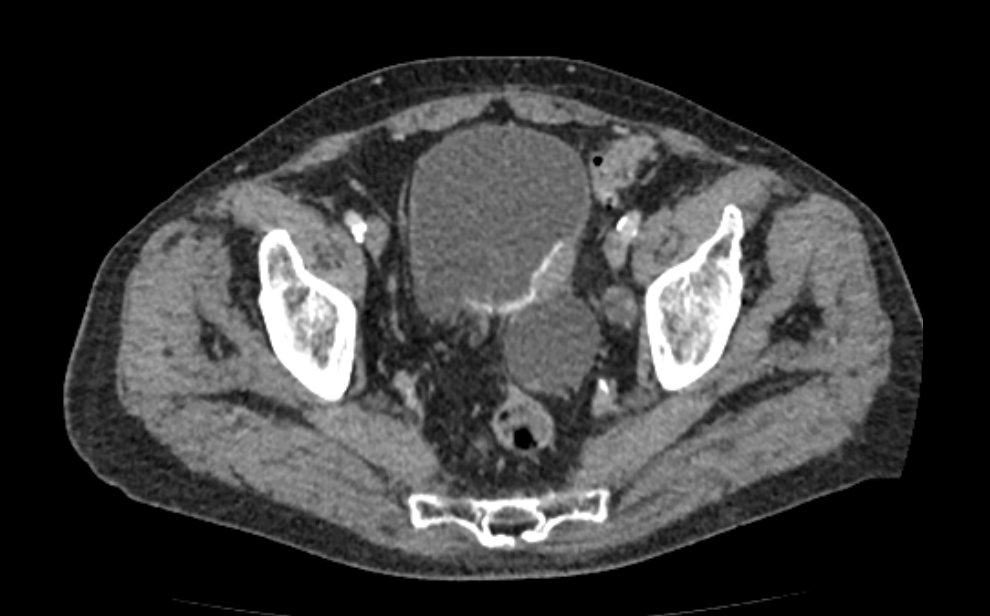

Мультиспиральная КТ мочевого пузыря является частью протокола обследования органов малого таза. Это высокоинформативный рентгенологический метод исследования, позволяющий детально визуализировать мочевой пузырь, нижнюю часть мочеточников, внутренние половые органы, прямую кишку.

Зачастую подобное исследование проводится при мочекаменной болезни (МКБ) для выявления конкрементов, определения их положения, размеров и плотности. Локализация конкремента существенно влияет на терапевтическое лечение МКБ, а наличие дивертикулов стенки мочевого пузыря на возможность самостоятельного выхода камня.

Также при данном исследовании возможно выявить утолщение стенки мочевого пузыря, что при диффузных изменениях может соответствовать проявлениям цистита, а локальные или неравномерные утолщения – характеризовать патологический процесс обусловленный новообразованиями.

Для улучшения визуализации патологических образований, в частности, при подозрении на опухолевый процесс, проводится внутривенное болюсное контрастирование. Методика контрастного усиления основана на введении в вену контрастного препарата, который в большей степени накапливается в патологически измененных участках и обеспечивает их яркую визуализацию на фоне здоровых тканей. Контрастирование дает возможность определить врачу границы опухоли, оценить степень прорастания в соседние органы и ткани, выявить опухоли минимальных размеров (как первичного, так и метастатического характера).

Что позволяет увидеть КТ мочевого пузыря

- цистит;

- дивертикулы мочевого пузыря

- цистоцеле

- уретероцеле

- варианты строения мочеточников

- камни мочевого пузыря;

- травмы, разрывы и растяжения органа;

- опухолевые новообразования.